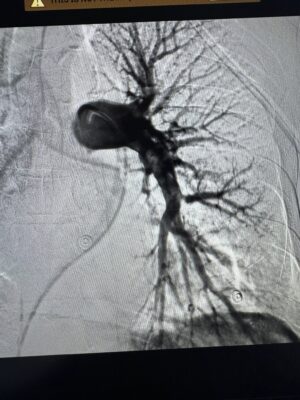

Команда фахівців вирішила провести малоінвазивну ендоваскулярну тромбаспірацію — процедуру, що дозволяє механічно видалити тромб із легеневої артерії без відкритої операції. Методика, яку лікарі нещодавно освоїли на конгресі інтервенційних радіологів у Барселоні, виконувалась під рентгенконтролем за допомогою катетера та спеціальної системи аспірації.